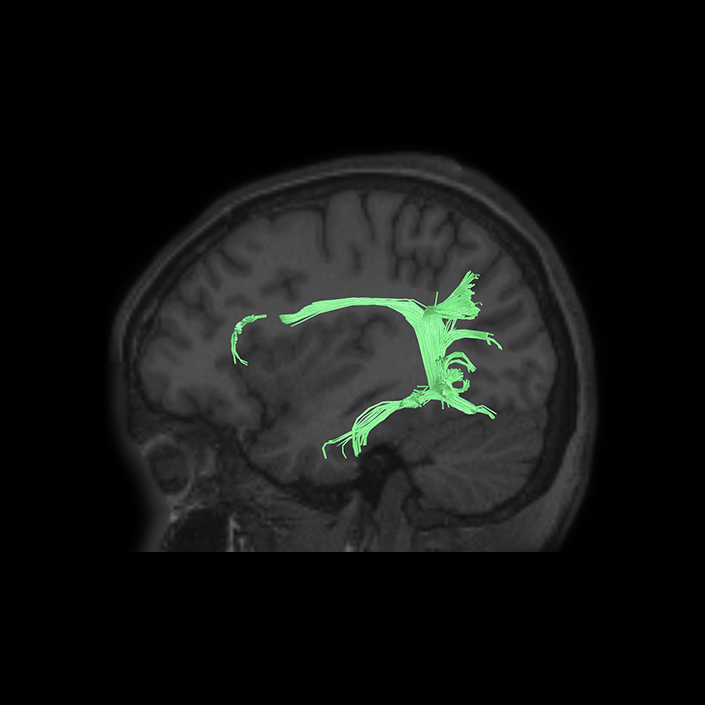

Disturbances of language have been linked to anatomic disruption of the human language network architecture for nearly 150 years.

Exploring the language organization in the brain began in the mid-19th century with Broca’s and Wernicke’s studies on patients with defined brain injuries and lesions in the mid-19th century.1,2 Further studies identified a neural tract, the arcuate fasciculus, for connecting Broca’s and Wernicke’s areas being one of the major components of language processing in humans.3 Later on, more studies confirmed and expanded these findings using additional techniques such as cortical intraoperative mapping,4 and subcortical mapping,5 and neuroimaging using DTI and fMRI. Using DTI, Rilling et al., (2008) found a noticeable temporal projection of arcuate fasciculus that is much smaller or absent in non-human primates.6 Further studies reported a strong left lateralization of arcuate fasciculus in humans.7

Additional invasive tests have been described to study impact on networks for clinical decision making. Historically injecting sodium amytal into one carotid artery (Wada Test) has been the gold standard for finding out the language lateralization in the brain.8 Studies found a very strong correlation between Wada test and language lateralization.9 More recently, similar findings have emerged using non-invasive neuro-imaging techniques. One study reported fMRI superiority over Wada test predicting postoperative language function in patients when fMRI and Wada test are not consistent with each other.10 Moreover, a recent guideline by the American Academy of Neurology suggested fMRI may be considered as a replacement of Wada test in epilepsy.11